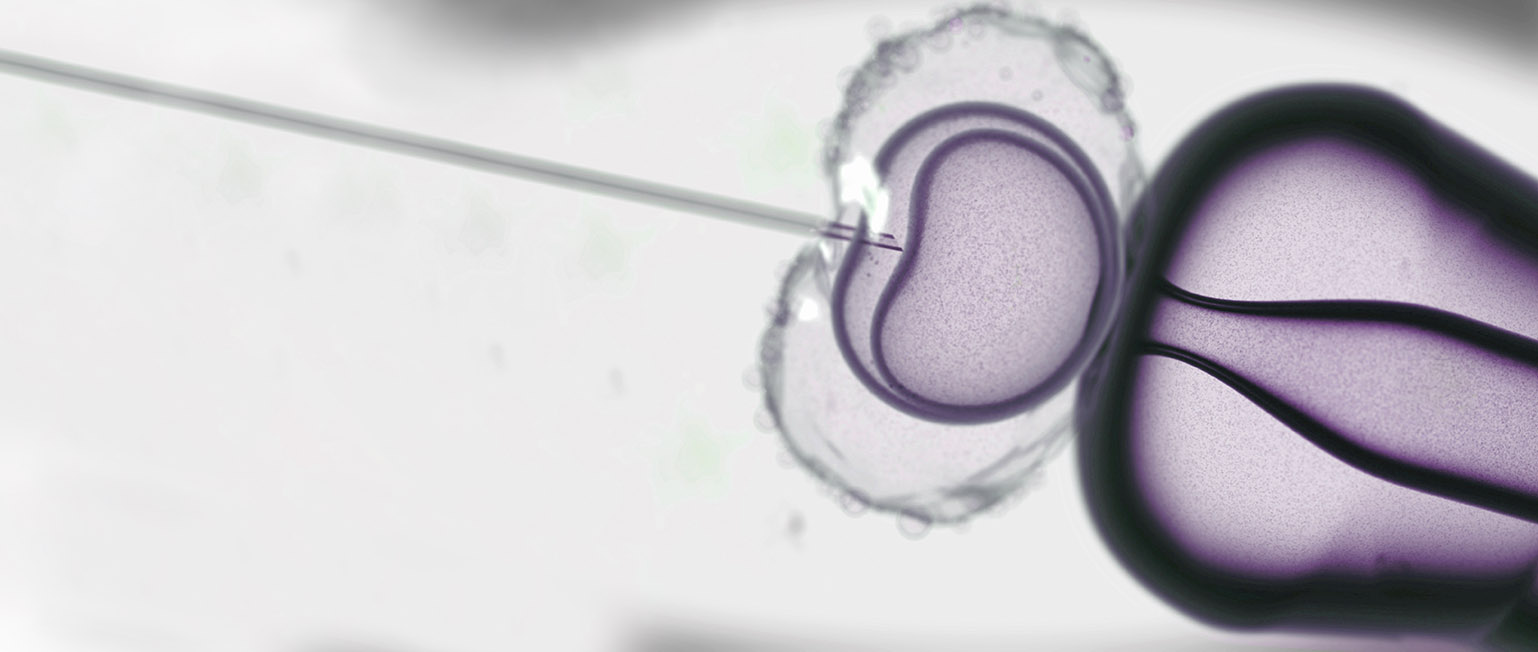

The key element of the IVF process involves the fertilization of the eggs “in vitro,” which simply means outside of the body. Eggs collected directly from the ovaries are combined with sperm in the laboratory to create embryos, which are then grown and nurtured in specialized incubators for three to five days before the best of the group is selected for transfer into the uterus, through the vagina and cervix.

- That same day, the eggs are fertilized with sperm in the laboratory and then placed in highly specialized incubators that carefully control their environment. The next morning, they are examined under a microscope to determine how many in the group fertilized successfully; on average 60-80% of the eggs that were fully mature can be expected to fertilize.